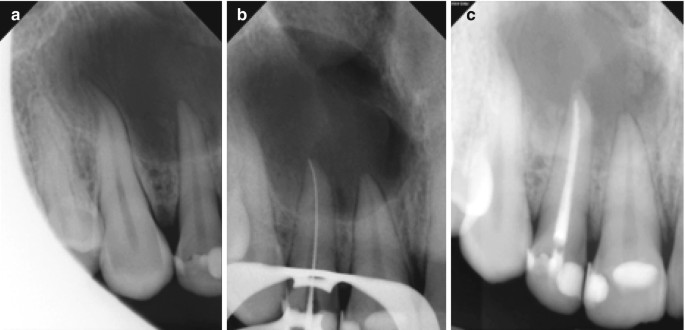

Endodontic Treatment Classification B Case Classification According Download Scientific Diagram

Endodontic Periodontic Lesion Management A Systematic Review Medicina Clinica Practica